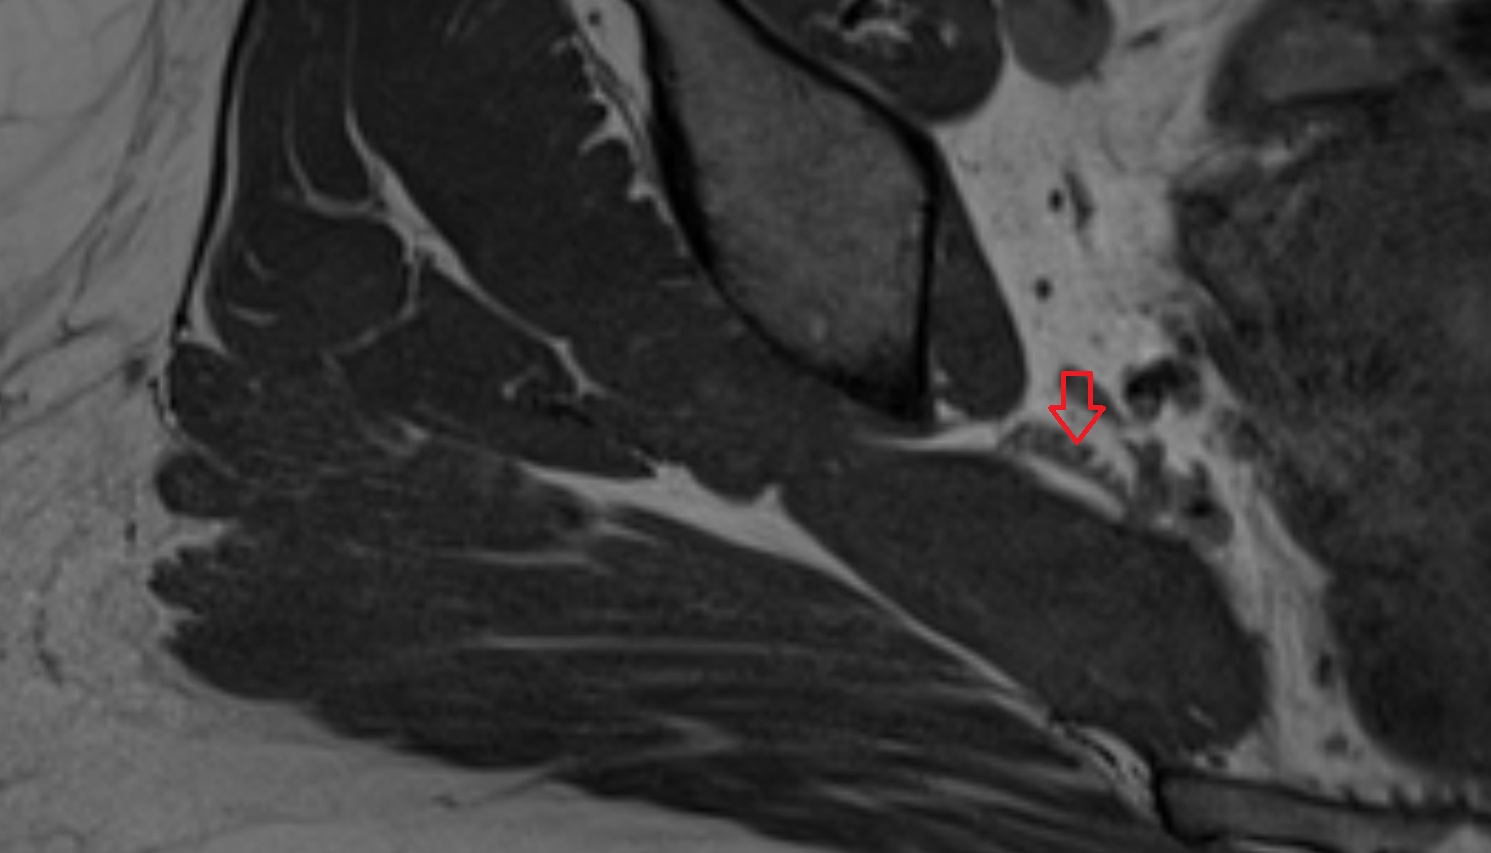

- Acetabular labrum